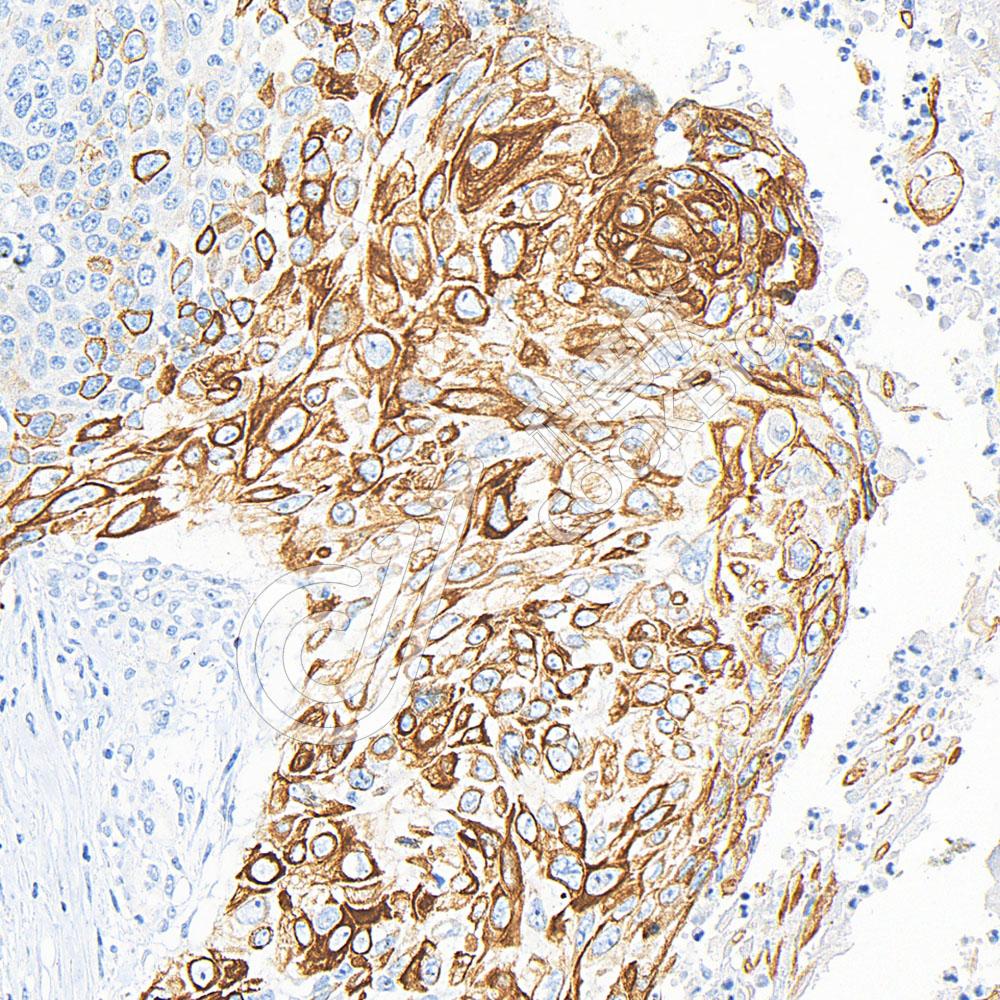

IHC检测Cytokeratin 16/K16蛋白(货号 K547415).

样品: 人食管癌, 4%多聚甲醛 (货号KSG1101) 固定12-24小时.

抗原修复: 柠檬酸抗原修复液(干粉, pH 6.0) (KSG1201), 高压锅均匀喷气计时2分钟.

—抗: 1: 800稀释, 4℃ 孵育过夜.

二抗: S-vision免疫组化多聚二抗(山羊抗小鼠), 即用型(货号KB3903), 室温孵育20分钟.